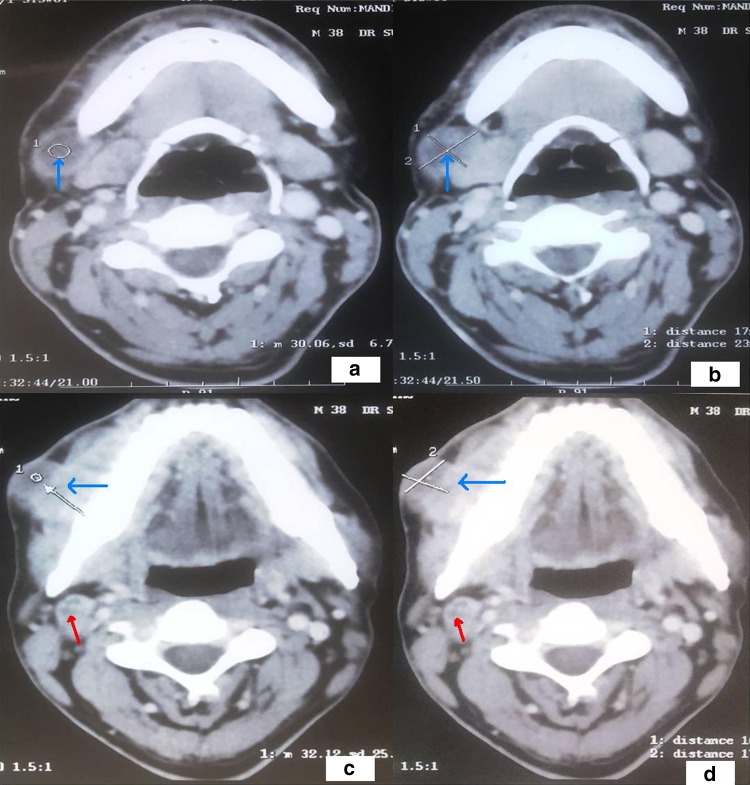

Now if we consider patients with ECS; 11 lymph node had ECS whereas 19 lymph node had no extra capsular spread on histopathological analysis. On analysis of these 19 lymph nodes without ECS we found that 11 lymph nodes had no central necrosis on the preoperative CT whereas remaining 8 lymph node were having central necrosis on CT and post op histopathology of these 8 lymph nodes showed only metastatic deposit, indicating the low specificity of the central necrosis in detection of the ECS (Tables 2, 3; Fig. 2a–d).

Fig. 2.

Photograph of histopathological examination (a, b) showing Lymph node with maintained normal architecture and no evidence of metastatic deposits or extracapsular spread [blue arrow] {H&E, 10X}, c showing Lymph node with metastatic deposits [red arrow] {H&E, 10X}and d showing Lymph node with metastatic deposits [red arrow] and cystification [red star] {H&E, 10X}

The best radiological predictor of lymph node metastasis is the finding of the central necrosis which has been reported to carry nearly 100% accuracy in predicting the presence of the metastatic disease [7, 8]. The detection of the malignant disease is based on the fact that as cancer cell invade the lymph node, its size shape and character changes so that as it enlarges, its centre dies and appears as necrosis, and there is the thin rim of the inflammation around edges, which shows up on scanning as the rim enhancement (Fig. 3a–d). On CT lymph node central necrosis is defined as a central area of the low attenuation surrounded by a rim of the enhancing tissue (Fig. 4a–d). The entities that mimic central necrosis are lipid metaplasia and abscess. Lipid metaplasia is the fatty degeneration secondary to the inflammation or irradiation and is usually found at the periphery of the lymph node, while central necrosis is in the centre. Abscess can be differentiated from central necrosis clinically.

Fig. 4.

CT scan neck axial view (a, b) showing central necrosis in the level 1B Lymph node [blue arrow], (c, d) showing Level 2 lymph node with central necrosis [red arrow] with a primary lesion in the right GB sulcus [blue arrow]